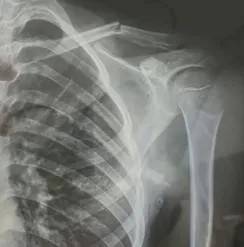

10月30日,内蒙古自治区赤峰市宁城县苏木皋小学一学生家长贾女士给记者打来电话,介绍了孩子被打的原因。贾女士称,放学通道的墙上有一个电灯的开关,好多孩子放学时都随手去拨弄开关。出于安全考虑,学校和老师都禁止孩子拨弄开关。23日放学时,他儿子和另一个同学调皮,再去拨弄了那个开关,被正在值班的另一个班的班主任发现,把她儿子打了,且打骨折了。

图片由报料者提供